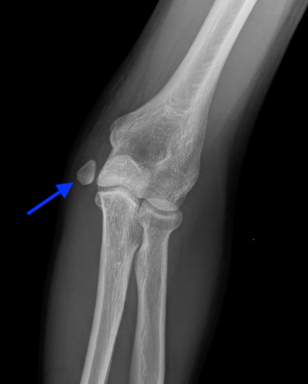

Medial Epicondyle Avulsion Fractures

- True fractures about the medial epicondyle typically occur between the age of 10-14 years

- This is a result of an acute injury typically associated with a discrete event such as a fall or a single throw

- X-rays demonstrate widening or displacement of the medial epicondyle

If left untreated, medial epicondyle fractures can develop into a nonunion